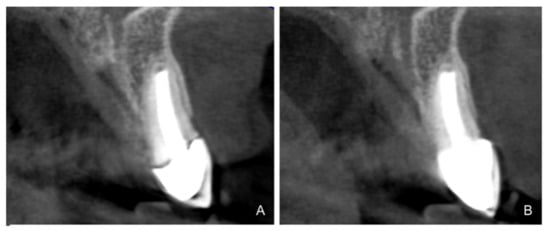

- Serra-Pastor, B.; Loi, I.; Fons-Font, A.; Solá-Ruíz, M.F.; Agustín-Panadero, R. Periodontal and prosthetic outcomes on teeth prepared with biologically oriented preparation technique: A 4-year follow-up prospective clinical study. J. Prosthodont. Res. 2019, 63, 415–420. [Google Scholar] [CrossRef] [PubMed]

- Agustín-Panadero, R.; Serra-Pastor, B.; Fons-Font, A.; Solá-Ruíz, M.F. Prospective Clinical Study of Zirconia Full-coverage Restorations on Teeth Prepared with Biologically Oriented Preparation Technique on Gingival Health: Results After Two-year Follow-up. Oper. Dent. 2018, 43, 482–487. [Google Scholar] [CrossRef] [PubMed]